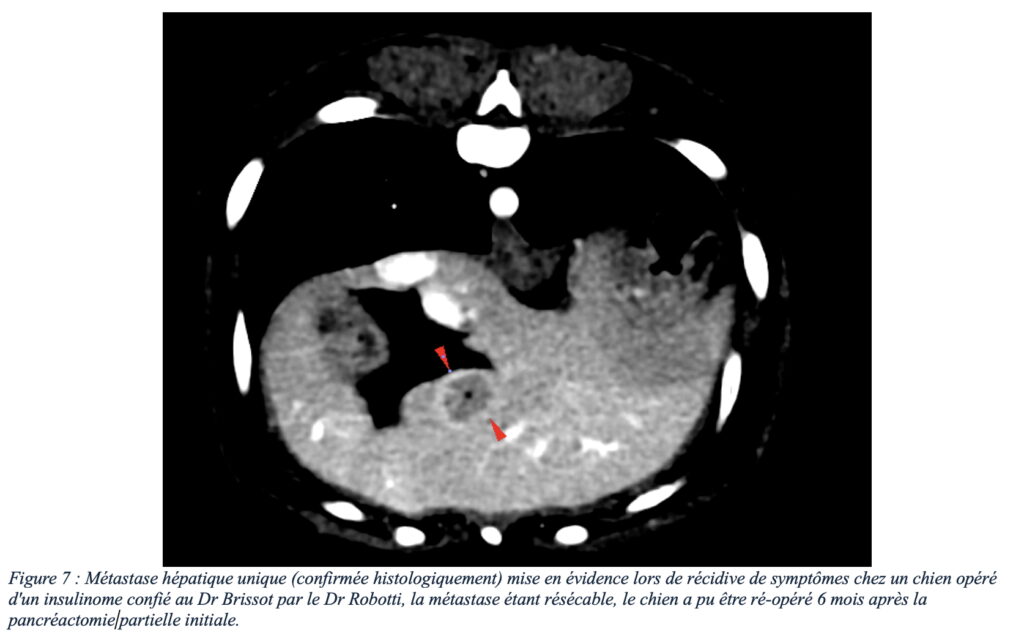

De l’expérience à Azurvet, certains animaux ont connu une première prise en charge chirurgicale couronnée de succès avec retour à une activité normale de l’animal. Certains de ces animaux ont même connu une récurrence des symptômes plusieurs mois après la chirurgie initiale, les examens d’imagerie ont ensuite mis en évidence un développement de récidive locale (figure 6) ou développement de métastases ganglionnaires et/ou hépatiques résécables (figure 7) permettant une seconde intervention, augmentant considérablement l’espérance de vie avec un confort satisfaisant.